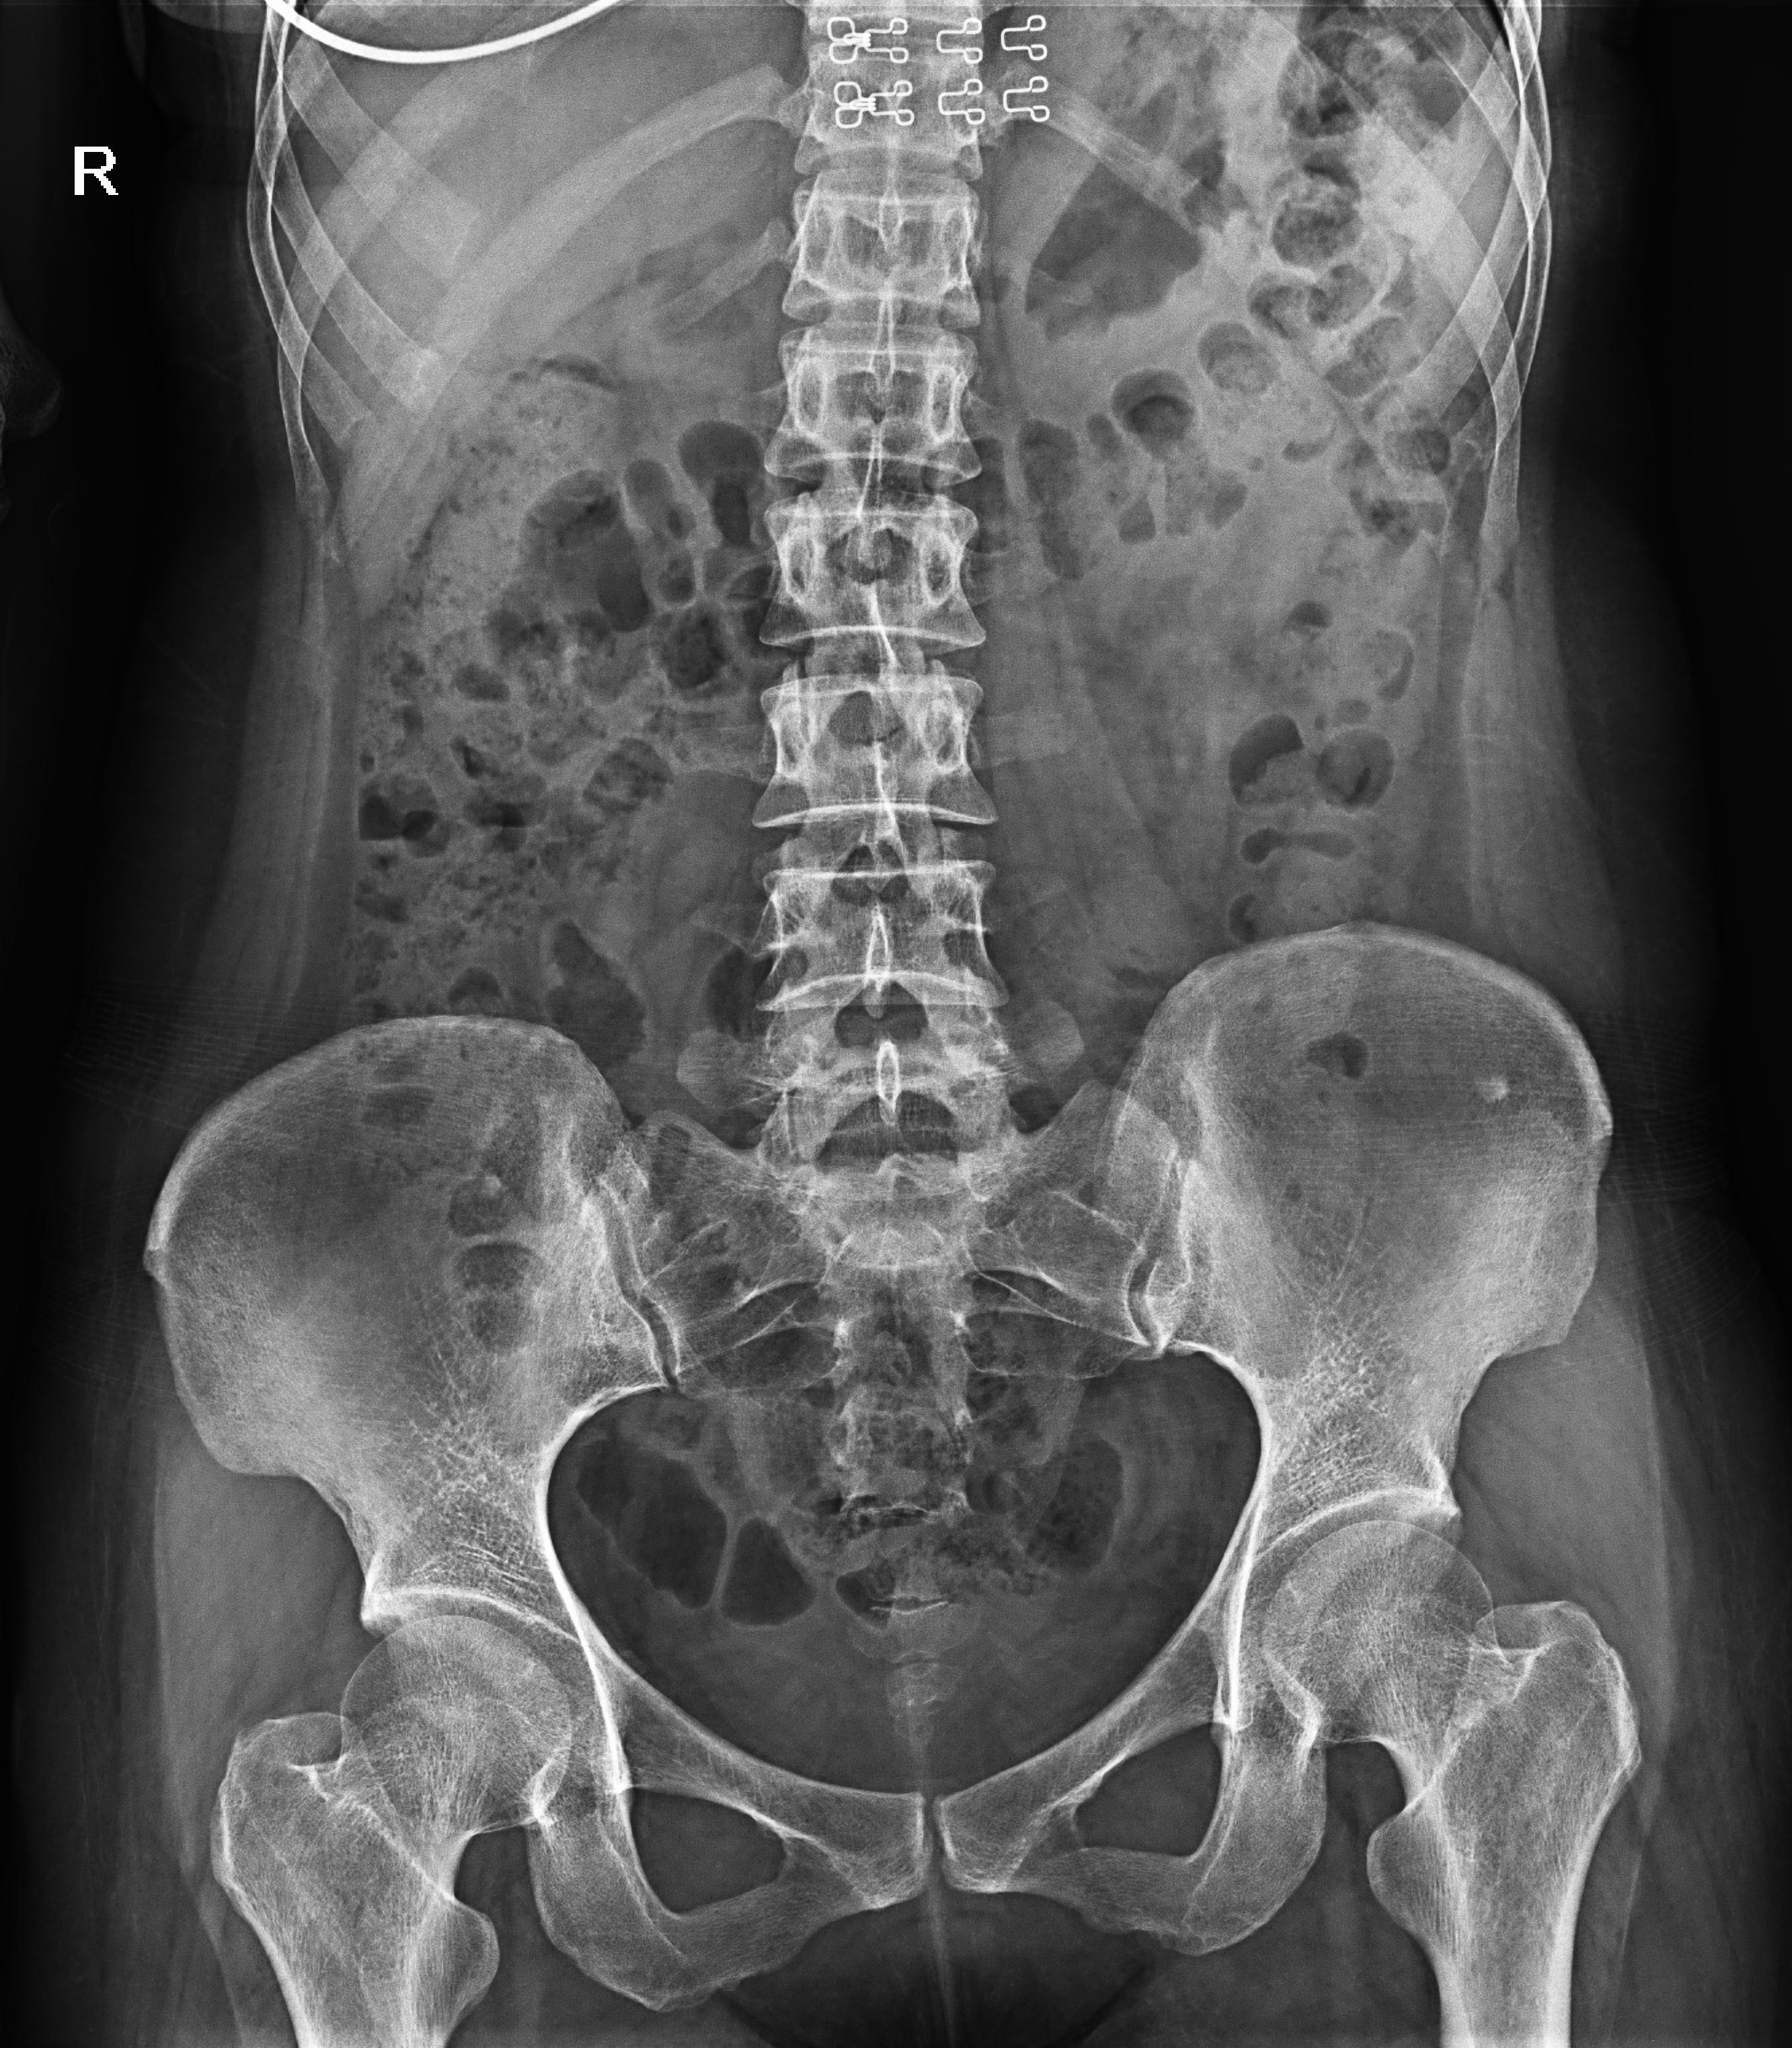

普利德醫(yī)療自主研發(fā)的新一代數(shù)字化X線透視攝影系統(tǒng),可應(yīng)用于DR攝影、數(shù)字透視、數(shù)字造影以及可視化精準(zhǔn)DR拍片等多種臨床X線檢查領(lǐng)域。

● 17*17英寸的超高清像素動(dòng)態(tài)平板探測(cè)器,更大的視野范圍,無(wú)需移動(dòng)即可觀察整個(gè)動(dòng)態(tài)過(guò)程,避免拖尾、噪聲對(duì)圖像的影響;

● 高效動(dòng)態(tài)平板技術(shù),圖像不會(huì)有幾何畸變,提供高分辨率和精確的圖像,為醫(yī)生臨床診斷提供精準(zhǔn)依據(jù);